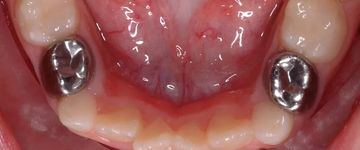

Урок 2.Pediatric restorative dentistry. Make good clinical decisions.

• Objectives of Restorative Treatments in primary Teeth;

• Criteria for Restorative Clinical Decisions;

• Medical and Clinical Management of Dental Caries;

• Caries Removal Concepts and clinical implications;

• Clinical Indications; limitations and Scientific Evidence:

1. Caries Arrest (Black Vs White);

2. Direct Restorations (Glass Ionomers and Composites);

3. Pre-made crowns (SSC and Zirconia Crowns);

• Clinical Techniques; Protocols and clinical difficulties:

1. SDF and Tiefenfluoride;

2. Atraumatic Restorative Treatment (ART);

3. Direct Restorations (Bulk fill Composites);

4. Pre- Made Crowns (SSC and Zirconia Crowns).

• Rubberdam Isolation.

Урок 9.Pediatric full mouth rehabilitation.

Upon completion of this course, participants will have learned:

1. Case selection and pre-operative risk assessment of the child patient.

2. To take decisions of treating the child patient under general anesthesia.

3. To be familiar with restorative procedures in primary and young permanent teeth with special emphasis on different and new techniques of restoration of mutilated anterior primary teeth.

4. To choose between the different techniques of pulp therapy in primary and young permanent teeth.

5. Methods of full coverage of primary teeth with special emphasis on laminated crowns and full ceramic crowns.

6. Special tips on full mouth treatment cases.

7. Post-operative care and hygiene instructions of the child patient after full mouth rehabilitation under general anesthesia.